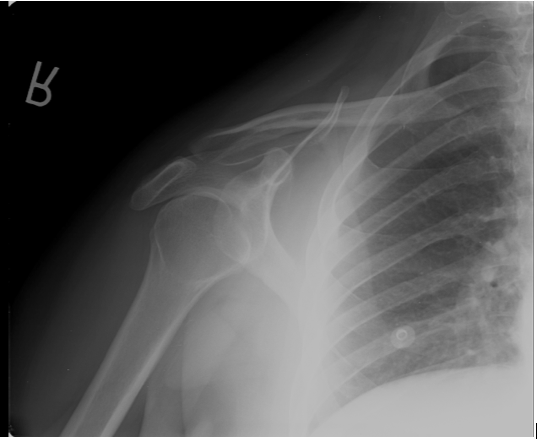

This is an example of a difficult to appreciate posterior dislocation. The humeral head appears to be in the Y. The clinical scenario, however, of pain and loss of range of motion after a seizure was highly suspicious for posterior dislocation, so further views are needed.